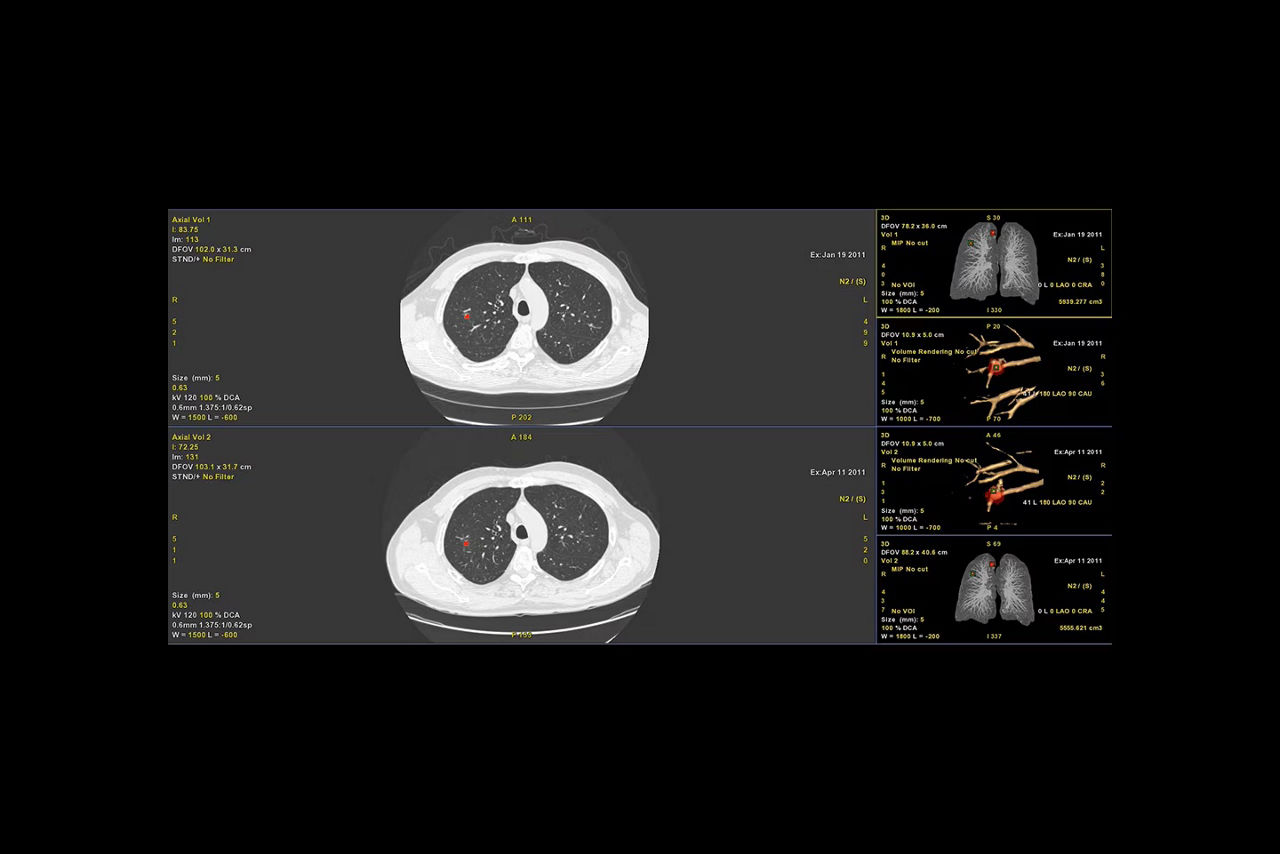

Efficient CT lung nodule assessment, diagnosis and follow-up.

Digital contrast agent (DCA)

Automatically highlights spherical shapes to visualize suspicious nodules

Automatic nodule segmentation

Provides automated segmentation and sizing of all nodules types

Automatic nodule analysis

Provides nodule information such as % growth, doubling time and volumes